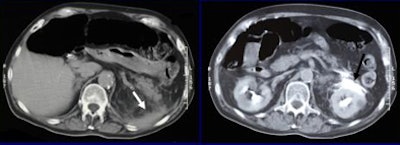

| A 45-year-old man after a car collision (left). Initial axial CT performed after splenic artery embolization (white arrow), shows a round area of increased attenuation in the spleen (black arrow).This finding was believed to represent active bleeding, but organ injury was not visible. Five-minute delayed scan (right) demonstrated intraperitoneal fluid, hematoma, and contrast material extravasation, confirming that the finding was secondary to delayed splenic rupture. The patient subsequently underwent splenectomy. All images and data courtesy of Dr. Alessandro Lemos. |